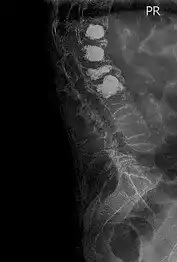

ezgif 5 4db50defb0Η σπονδυλοπλαστική είναι μία διαδερμική τεχνική που εφαρμόζεται σε περιπτώσεις σπονδυλικών καταγμάτων.

Είναι δυνατόν να εκτελεστεί υπό τοπική η γενική (συνήθως) αναισθησία. Υπό ακτινοσκοπική καθοδήγηση εισάγεται μία ειδική βελόνη έως τον πάσχοντα σπόνδυλο. Όταν προσεγγίσει το ακριβές σημείο, εγχύεται μέσω αυτή της βελόνης οστικό τσιμέντο στον κατεστραμμένο σπόνδυλο, το οποίο σκληραίνει άμεσα, σταθεροποιώντας τα κατάγματα. Είναι δυνατό να απαιτείται η λήψη βιοψίας πριν την έναρξη έγχυσης οστικού τσιμέντου.

Η ανακούφιση από τον πόνο είναι εντυπωσιακή, ενώ σταματά η εξέλιξη της κύρτωσης που συνοδεύει συνήθως τις περιπτώσεις συμπιεστικών καταγμάτων.